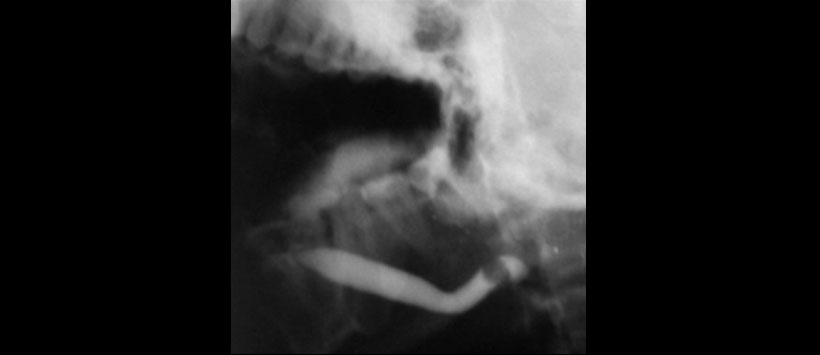

Figura 1: Sialograma convencional que muestra un defecto de llenado de forma ovalada (debido al cálculo) que obstruye casi toda la luz del conducto izquierdo de Wharton. El conducto de Wharton está dilatado proximal a la obstrucción (imagen original)